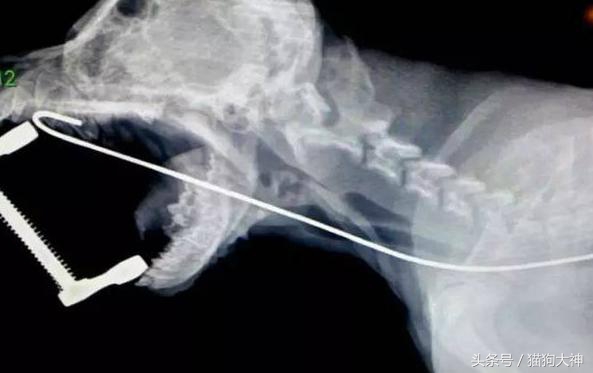

前两天,一只小腊肠去打疫苗,却意外捡回了一条命!因为在打疫苗过程中,主人和医生聊天说狗狗拆了自己的键盘,结果好多零件都找不到了,主治医师一听不对,赶紧安排狗狗拍片和手术。

这就是从狗狗胃里取出的零件,几乎塞满了小家伙的胃,再晚发现可能就要悲剧了。